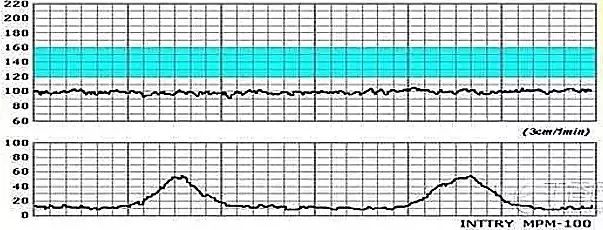

胎心胎动宫缩图

图片尺寸720x540